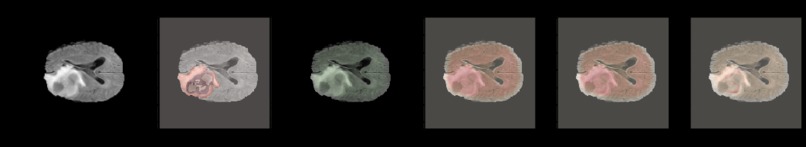

Segmenting tumor in brain MRI scans and then visualizing it using 3D models

We used tensorflow for modelling and simple itk for visualization and python for volumetric analysis.

3D rendering of the brain and tumor using segmented images made by our model.